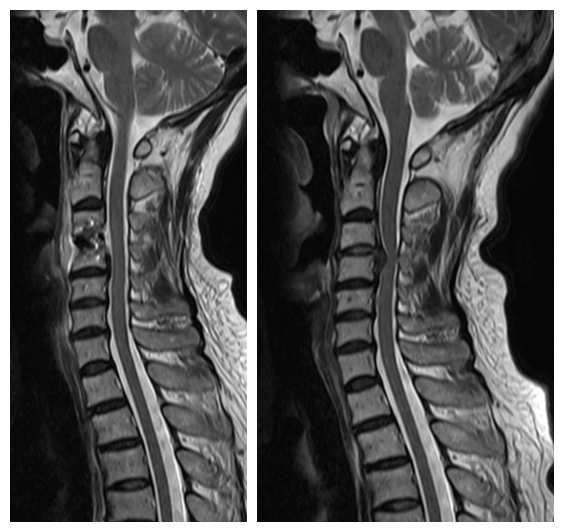

刘女士家属知道惠州市第三人民医院有个专治颈肩腰腿疼痛的科室,即来颈肩腰腿痛门诊就诊,入院后MRI示:颈3/4椎间盘变性并向后下脱出,颈3/4-6/7水平椎管狭窄及双侧神经根受压,以颈3/4水平狭窄为著。

术前MRI 和术后MRI

惠州市第三人民医院骨科医学中心主任武明鑫博士、颈肩腰腿痛科许球祥主任、孙进主治医师,详细询问刘女士病史、细致体格检查、仔细阅读辅助检查,经认真分析讨论,诊断为“脊髓型颈椎病”,认为刘女士病情目前并不适合继续保守治疗,建议行骨科中心阶梯疗法中的开放手治疗方案。